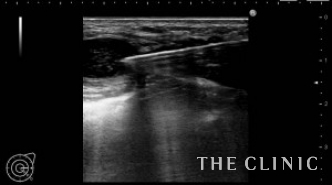

5年前にヒアルロン酸豊胸を受けられ、しこりになってしまったためしこり除去をご希望でご来院されました。ヒアルロン酸のしこりが大量にある場合は、しこり治療とCRF注入を同時に行うことにより脂肪壊死やしこりのリスクが高くなります。この方の場合は、少量のヒアルロン酸であったため、同時CRF注入を行いました。写真)エコー下にヒアルロニダーゼを注入します。

ヒアルロニダーゼがヒアルロン酸に混ざると、すぐに水様になるため吸引除去します。